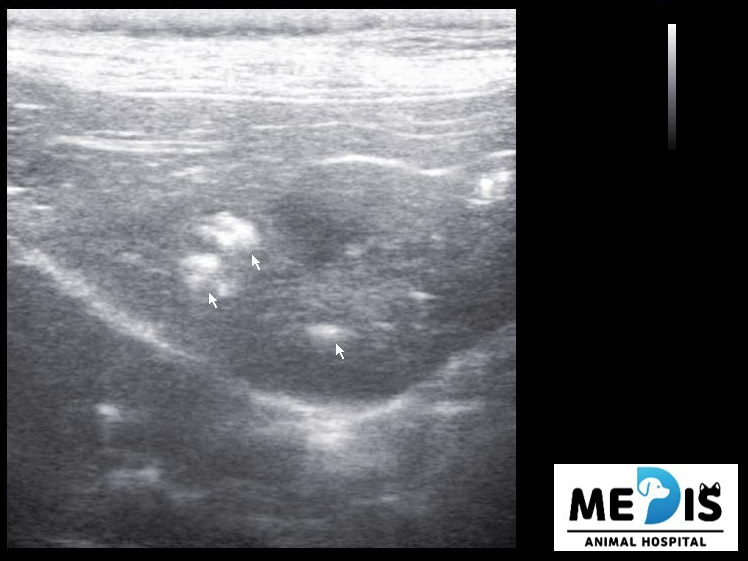

초음파에서도 담낭 주변이나 간 내부의 담도에 결석으로 의심되는 음영이 다수 관찰됐습니다.

보다 정확한 위치, 분포등을 확인하기 위해서 CT 촬영을 실시했습니다.

출처 : 경기동물영상센터 CT소견 CT검사에서 간 우측 내측엽 담도 내 다량의 결석이 확인되었습니다.